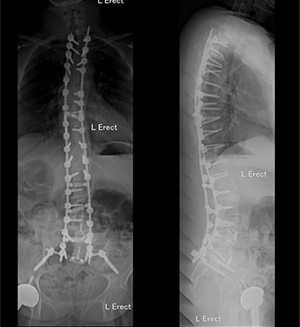

Since 2008, two of the authors have been performing Dual-Surgeon Deformity Surgery (DSDS) at North Shore Private Hospital. Over the last 10 years, with the additional of our third author in 2014, we have performed over 500 Dual-Surgeon procedures at North Shore Private Hospital. There has been no deep infections that required return to theatre in the DSDS group. The average surgical time is less than 4 hours and 25 minutes.

Pre-operative planning plays a major role in reducing surgical time and achieving maximum efficiency in the operating theatre. The surgical team is comprised of regular members of nursing and anaesthetic staff who are experience in all the different aspects of DSDS and are able to coordinate multiple tasks efficiently.

Surgery is performed in both a simultaneous and tandem manner. Each patient’s procedure is tailored to their anatomy and their needs, and different steps of the operation (such as decompression, osteotomies, correction and screw placement) are simultaneously carried out in concert. The surgical team needs to be able to cater to two surgeons performing different steps of the operation at the same time.

DSDS technique has been successful in safely minimizing overall operative time while achieving the surgical goal with a reduced infection rate.